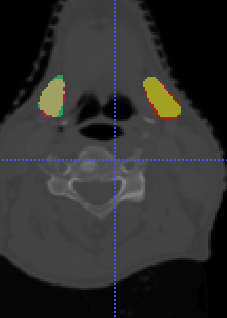

In Chapter 6, we propose an end-to-end, atlas-free 3D convolutional deep learning framework for fast and fully automated whole-volume HaN anatomy segmentation [115]. Our deep learning model, called AnatomyNet, segments OARs from head and neck CT images in an end-to-end fashion, receiving whole-volume HaN CT images as input and generating masks of all OARs of interest in one shot. AnatomyNet is built upon the popular 3D U-net architecture, but extends it in three important ways: 1) a new encoding scheme to allow auto-segmentation on whole-volume CT images instead of local patches or subsets of slices, 2) incorporating 3D squeeze-and-excitation residual blocks in encoding layers for better feature representation, and 3) a new loss function combining Dice scores and focal loss to facilitate the training of the neural model. These features are designed to address two main challenges in deep-learning-based HaN segmentation: a) segmenting small anatomies (i.e., optic chiasm and optic nerves) occupying only a few slices, and b) training with inconsistent data annotations with missing ground truth for some anatomical structures. We collect 261 HaN CT images to train AnatomyNet, and use MICCAI Head and Neck Auto Segmentation Challenge 2015 as a benchmark dataset to evaluate the performance of AnatomyNet. The objective is to segment nine anatomies: brain stem, chiasm, mandible, optic nerve left, optic nerve right, parotid gland left, parotid gland right, submandibular gland left, and submandibular gland right. Compared to previous state-of-the-art results from the MICCAI 2015 competition, AnatomyNet increases Dice similarity coefficient by 3.3% on average. AnatomyNet takes about 0.12 seconds to fully segment a head and neck CT image of dimension , significantly faster than previous methods. In addition, the model is able to process whole-volume CT images and delineate all OARs in one pass, requiring little pre- or post-processing. We demonstrate that our proposed model can improve segmentation accuracy and simplify the auto-segmentation pipeline. These contributions are released as an open-source software package called AnatomyNet, which is publicly available555https://github.com/wentaozhu/AnatomyNet-for-anatomical-segmentation. Portions of this chapter were published as part of [115].

- [121] W. Zhu and X. Xie. Adversarial deep structural networks for mammographic mass segmentation. arXiv:1612.05970, 2016.